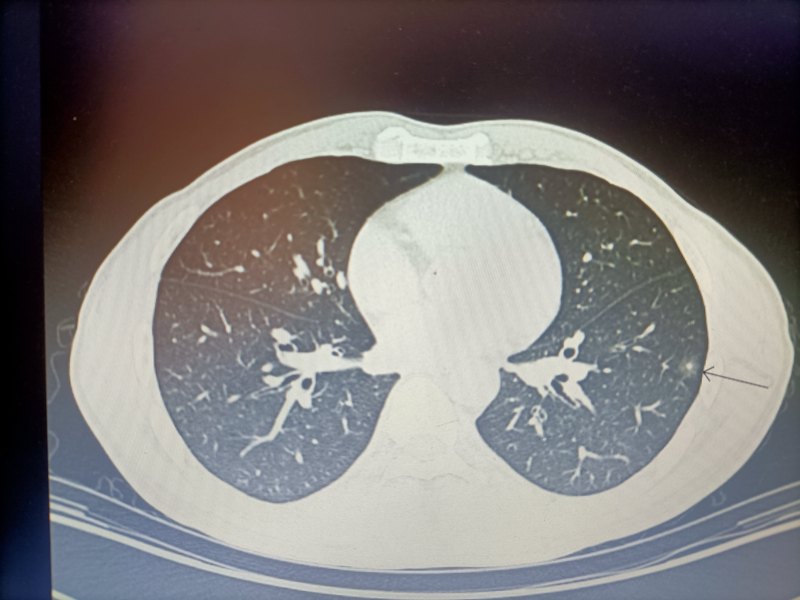

- 精選 肺結(jié)節(jié)門診的常見問題

在門診,常會(huì)遇到這樣的患者:因體檢發(fā)現(xiàn)肺結(jié)節(jié);又或是因外傷意外發(fā)現(xiàn)肺結(jié)節(jié);還或是因就診其他疾病時(shí)發(fā)現(xiàn)肺結(jié)節(jié)。對(duì)于猝不及防出現(xiàn)的肺結(jié)節(jié),他們往往充滿疑問。究竟肺結(jié)節(jié)到底是什么?會(huì)不會(huì)癌變?……今天就來帶大家了解有關(guān)肺結(jié)節(jié)的那些問題。1.問:發(fā)現(xiàn)肺結(jié)節(jié)怎么辦?答:肺結(jié)節(jié)是胸部影像學(xué)上一個(gè)非常常見的表現(xiàn)。人群中發(fā)現(xiàn)肺結(jié)節(jié)的比例約在20%左右,近年來這個(gè)比例在不斷上升,當(dāng)然我在這里要糾正一個(gè)誤區(qū),就是說這并不是肺結(jié)節(jié)的發(fā)病率增加了,而是隨著體檢意識(shí)、胸部CT的普及,在發(fā)現(xiàn)肺結(jié)節(jié)的幾率更大了。在所有肺結(jié)節(jié)的人群中,95%以上的都為良性結(jié)節(jié),只有5%左右為惡性,這些惡性的肺結(jié)節(jié)如果可以及早的發(fā)現(xiàn),也基本上屬于早期的肺癌,比如原位癌、微浸潤癌等,通過及時(shí)的干預(yù)基本上可以做到痊愈,所以發(fā)現(xiàn)肺結(jié)節(jié)后不要驚慌,只要規(guī)范的到胸外科??崎T診就醫(yī),就能得到合理的處理。2.問:剛才您提到95%以上的肺結(jié)節(jié)是良性的,那么怎么來判斷其良性及惡性,這些肺結(jié)節(jié)都有些什么樣的病因呢?他們后續(xù)需要如何的規(guī)范處理?答:肺結(jié)節(jié)比較多見的是炎性結(jié)節(jié),比如近期有下呼吸道的感染,會(huì)出現(xiàn)短時(shí)間的結(jié)節(jié),這種結(jié)節(jié)通過抗炎治療,一部分可以在短期內(nèi)消失;還有一部分會(huì)隨著炎癥吸收遺留結(jié)節(jié)樣改變,但是通常不會(huì)再長大;還有一部分為吸入性結(jié)節(jié),如吸入粉塵、煤灰等,這些吸入物會(huì)在肺內(nèi)沉淀、包裹形成結(jié)節(jié),這種結(jié)節(jié)一部分會(huì)逐漸增大。以上的結(jié)節(jié)都是良性的,而極少部分結(jié)節(jié)為早期肺癌形成的結(jié)節(jié)。通常我們一般根據(jù)結(jié)節(jié)的生長速度與方式、邊緣形態(tài)、內(nèi)部密度、周圍血管結(jié)構(gòu)等方面進(jìn)行動(dòng)態(tài)的分析,判斷肺結(jié)節(jié)的性質(zhì)。當(dāng)發(fā)現(xiàn)結(jié)節(jié)形態(tài)不規(guī)則,有分葉和毛刺等特征,結(jié)節(jié)惡性可能性較大時(shí)我們需要及時(shí)干預(yù),而通過觀察發(fā)現(xiàn)其為惡性的可能性較小時(shí),一般建議患者定期查胸部的薄層CT。通常根據(jù)肺結(jié)節(jié)的大小及性質(zhì),給予定期的復(fù)查以明確是否存在惡性的可能。一般較大的肺結(jié)節(jié)需要3個(gè)月復(fù)查一次,較小的結(jié)節(jié)可以半年或1年復(fù)查一次,但是如果患者存在肺癌的高危因素,比如:有肺癌家族史、長期吸煙、長期接觸過致癌物等,則其復(fù)查的時(shí)間需要縮短。3.問:肺結(jié)節(jié)不可以拍胸片檢查嗎?畢竟從費(fèi)用上來說,胸片更加經(jīng)濟(jì)。答:肺結(jié)節(jié)是不建議使用胸片的篩查的,因?yàn)榉谓Y(jié)節(jié)本身病灶較小,極其容易被肋骨、肩胛骨或者心臟的影像干擾,漏診率較高。4.問:如果考慮惡性結(jié)節(jié)可能性較大?咱們應(yīng)該怎么處理?答:若結(jié)節(jié)的影像特征存在惡性表現(xiàn)時(shí),建議應(yīng)早期進(jìn)行手術(shù)治療;若影像特征不是很明顯,不能排除惡性可能時(shí),我們可以到胸外科專家門診就診,通過專家豐富的病理-影像經(jīng)驗(yàn),一般都可以明確診斷,若考慮為惡性,則需要給予切除。5.問:肺結(jié)節(jié)手術(shù)一般采用什么樣的手術(shù)方式?答:考慮惡性的肺結(jié)節(jié)首選的處理方式為胸腔鏡微創(chuàng)手術(shù),手術(shù)時(shí)只需一個(gè)2-3cm操作孔,行肺葉或肺段切除術(shù),療效明確,通常可以達(dá)到治愈不再復(fù)發(fā),如果患者因?yàn)楦啐g、身體素質(zhì)差、還可以選擇經(jīng)皮消融治療,這種治療創(chuàng)傷性更小,更加適用于高齡等不能耐受手術(shù)的患者。